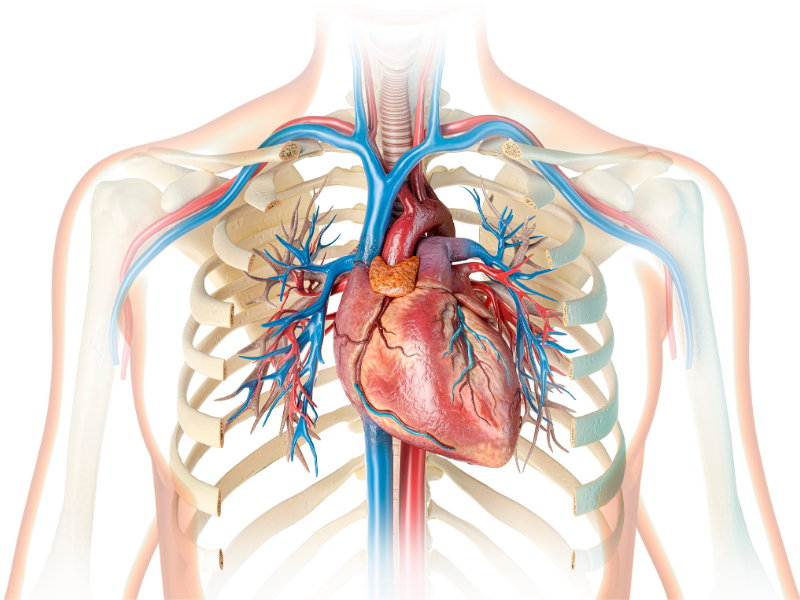

Yaşamımız boyunca kalbimiz durmaksızın çalışır ve tüm organlarımıza kan pompalar. Kalp kası yorulmaz fakat sürekli enerjiye ihtiyaç duyar. İşte kalbin bu şekilde çalışabilmesi için diğer organlarda olduğu gibi kanlanması gerekir. Kalp kasını besleyen damarlara koroner arterler diyoruz.

Koroner arterlerin iç yüzeyleri pürüzsüzdür ve kan akışı sorunsuz seyreder. Aynı zamanda damar içini döşeyen hücreler damarın açık kalmasını sağlayan maddeler salgılarlar. Koroner damarların çok farklı etkenler ve mekanizmalar sonucunda daralması sonucunda ateroskleroz (damar sertliği) dediğimiz damar tıkanıklığı başlamış olur. Ateroskleroz dediğimiz olay başladığında damarın elastikiyeti de azalır ve ihtiyaç halinde fazla kan geçişi için genişlemesi gereken damarlar bunu yapamazlar. Bütün bunların net sonucu kişi efor yaptığında kalbin buna cevap verebilmesi için gerekli kan kalp kasına gidemez ve belirtiler başlar.